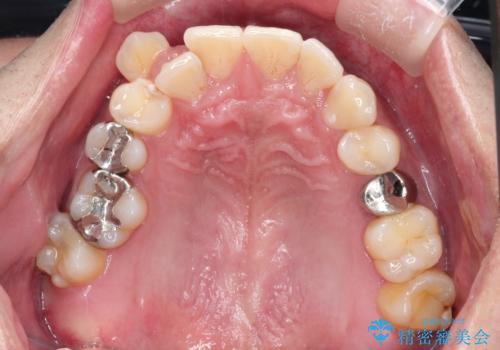

【ワイヤー矯正】八重歯と下の歯の凸凹を治したい

- 主訴:右上の八重歯と、下の歯の凸凹を治したい

上顎右側第一小臼歯と下顎右側第一小臼歯を抜歯しワイヤー矯正を行いました。

右側2級、左側1関係だったため、右側上下第一小臼歯を抜歯し、ワイヤー矯正を行いました。

期間:2年6カ月